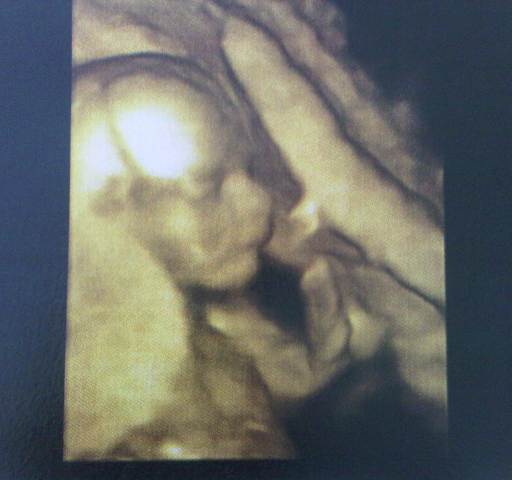

18+6

kuki

Ki is van odabent